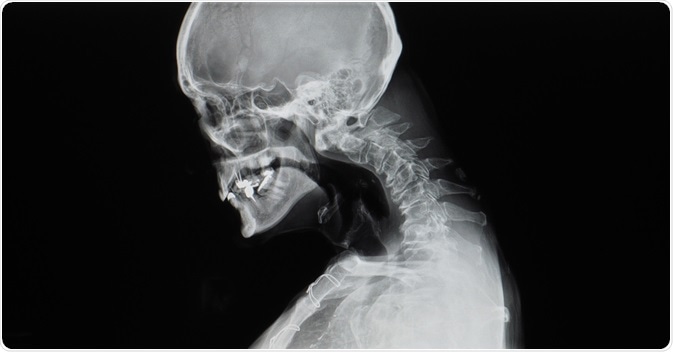

Image Credit: Yok_onepiece / Shutterstock.com

Usually, full-length anteroposterior and lateral radiographs are ordered to allow for proper visualization of the spinal structure. Computerized tomography (CT) of the spine provides supplemental information on eventual bone abnormalities predating or caused by kyphosis. With magnetic resonance imaging (MRI), it is possible to assess the junction of the spinal joints and determine if there is an impingement on the spinal canal of bone structures.